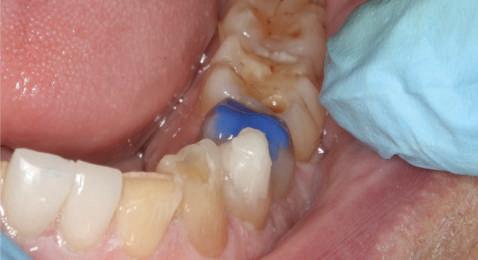

Atitudine: Fiecare bont individualizat s-a aplicat pe câte un analog de implant. Fig. 6 prezintă bontul nou preparat pe analogul său cu inel de cupru de dimensiuni mari pentru a susţine

materialul de amprentare (alternativ, s-ar fi putut utiliza o lingură de amprentare universală pe cadran pentru a asigura suport pentru materialul de amprentare). Fig. 7 prezintă bontul individualizat cu ceară aplicată pentru a preveni pătrunderea materialului de amprentare în camera de acces a şurubului, iar fig. 8 ilustrează tehnica de amprentare care evită necesitatea plasării unui şnur de retracţie în şanţ în jurul implantului. Această tehnică este, de asemenea, utilă pentru adăugarea la marginile restaurării provizorii.

Cazul (2): Repreparea intraorală a bonturilor cu amprente extraorale

Figurile

6. Bontul nou preparat pe analog.

7. Bont individualizat cu vată şi ceară.

8. Tehnica de amprentare.